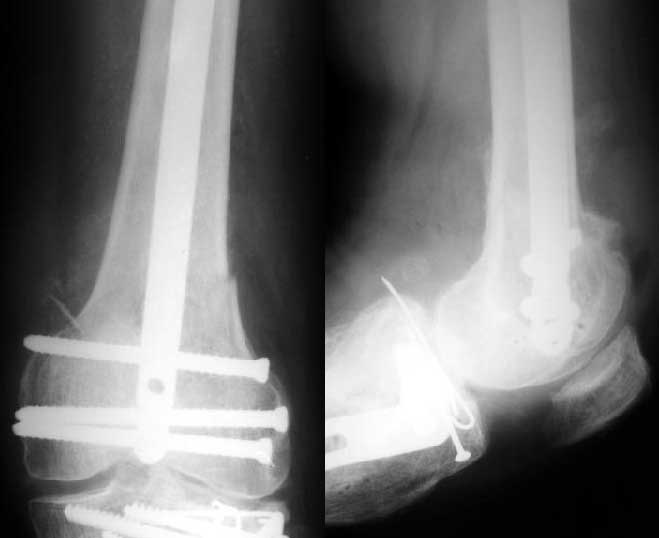

Думаю лучше зафиксировать мыщелковой клинковой пластиной 95 градусов или DCS. Трудно представить, как удастся закрепить дистальный отломок гвоздем.

Можно и мыщелковой, и клинковой 90-градусной. Не хотелось бы только разрезов обширных, да скелетирования отломков.

Вот новые пластинки LCP скорее раздобыть бы, с угловой стабильностью которые можно вводить подмышечно через небольшой разрез...

S> Трудно представить , как удастся закрепить дистальный отломок гвоздем

Винтами. Снимок в приложении.